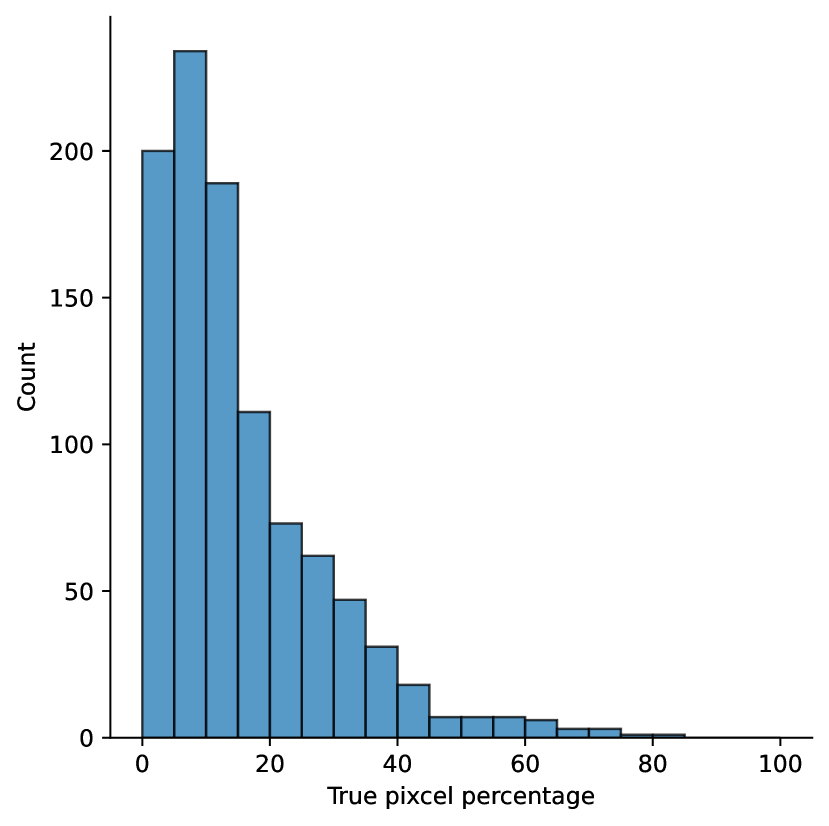

A few sample images and the corresponding masks of the polyp dataset in HyperKvasir are shown in Fig 2. The polyp images are RGB images. The masks of the polyp images are single-channel images with white () for true pixels, which represent polyp regions, and black () for false pixels, which represent clean colon or background regions. In this dataset, there are different sizes of polyps. The distribution of polyp sizes as a percentage of the full image size is presented in the histogram plot in Fig 3, and we can observe that there are more relatively small polyps compared to larger polyps. Additionally, a subset of this dataset was used to prove that the performance of segmentation models trained with small datasets can be improved using our SinGAN-Seg pipeline, and the whole dataset was used to show the effect of using SinGAN-Seg generated synthetic images instead of a large dataset which has enough data to train segmentation models. In this regard, this dataset was used for two purposes:

To understand the difference between the mask distribution of real images and synthetic images, we plotted pixel distribution of masks of synthetic images in Fig 6. This plot is comparable to the pixel distribution presented in Fig 3. The randomness of the generations made differences in the distribution of true pixel percentages compared to the true pixel distribution of real masks of real images. However, the overall shape of synthetic data mask distribution shows a more or less similar distribution pattern to the real true pixel percentage distribution.